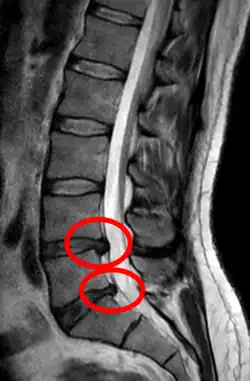

Lumbar disc herniations occur in the back, most often between the fourth and fifth lumbar vertebral bodies or between the fifth and the sacrum. Here, symptoms can be felt in the lower back, buttocks, thigh, anal/genital region (via the perineal nerve), and may radiate into the foot and/or toe. The sciatic nerve is the most commonly affected nerve, causing symptoms of sciatica. The femoral nerve can also be affected and cause the patient to experience a numb, tingling feeling throughout one or both legs and even feet or a burning feeling in the hips and legs.[22] A herniation in the lumbar region often compresses the nerve root exiting at the level below the disc. Thus, a herniation of the L4–5 disc compresses the L5 nerve root, only if the herniation is posterolateral.

• Magnetic resonance imaging is the gold standard study for confirming a suspected LDH. With a diagnostic accuracy of 97%, it is the most sensitive study to visualize a herniated disc due to its significant ability in soft tissue visualization. MRI also has higher inter-observer reliability than other imaging modalities. It suggests disc herniation when it shows an increased T2-weighted signal at the posterior 10% of the disc. Degenerative disc diseases have shown a correlation with Modic type 1 changes. When evaluating for postoperative lumbar radiculopathies, the recommendation is that the MRI is performed with contrast unless otherwise contraindicated. MRI is more effective than CT in distinguishing inflammatory, malignant, or inflammatory etiologies of LDH. It is indicated relatively early in the course of evaluation (<8 weeks) when the patient presents with relative indications like significant pain, neurological motor deficits, and cauda equina syndrome. Diffusion tensor imaging is a type of MRI sequence used for detecting microstructural changes in the nerve root. It may be beneficial in understanding the changes that occur after herniated lumbar disc compresses a nerve root, and might help in differentiating the patients that need surgical intervention. In patients with a high suspicion of radiculopathy due to lumbar disc herniation, yet the MRI is equivocal or negative, nerve conduction studies are indicated.[44] T2-weighted images allow for clear visualization of protruded disc material in the spinal canal.